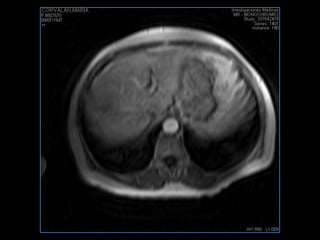

LIC ALEJANDRA GALVEZ RM DE ABDOMEN

PROTOCOLO abdomen COR T2, AXIAL supresion grasa AX T1 +SAG T2  CON   GADOLINIO :  COR T1+AX T1(DIN) SAT: NO  FASE: RL THK: 6MM  COIL:  GAP: (FACTOR 1.4) 2MM FOV: 40 CM NEX:2 SINCRONIZACION RESPIRATORIA EN 3 O 4 CICLOS ALE

resonancia de abdomen